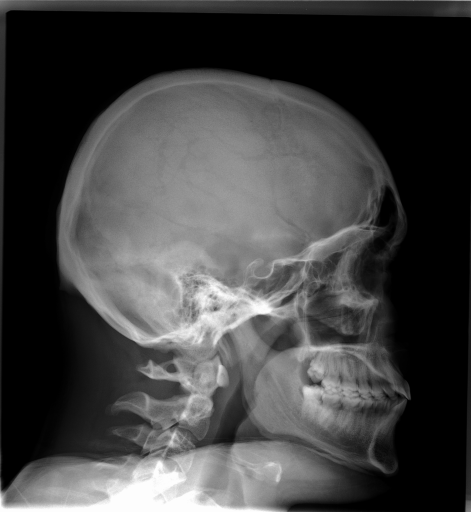

Image Dataset – The Image Retrieval in Medical Applications (IRMA) 2009 database is a collection of 14,410 x-ray images that have been randomly collected from daily routine work at the Department of Diagnostic Radiology of the RWTH Aachen University (Fig. 2). The downscaled images were collected from different ages, genders, view positions, and pathologies [33]. Each image in the dataset has an IRMA code. According to these codes, 193 classes are defined according to 2008 IRMA codes. The IRMA code comprises four axes with three to four positions each: 1) the technical code (T) (modality), 2) the directional code (D) (body orientations), 3) the anatomical code (A) (body region), and 4) the biological code (B) (the biological system examined). The complete IRMA code consists of 13 characters TTTT-DDD-AAA-BBB, with each character in . As many as 12,677 images are separated for training. The remaining 1,733 images are used as test data. In this project, the IRMA 2009 dataset has been used with specified 2008 IRMA labels (consisting of 193 classes) for retrieval purposes. Otherwise, same dataset is utilized with general 2005 IRMA labels (consisting of 57 classes) for classification purpose. 2005 IRMA labels are more general than 2008 IRMA labels because it has been made of 6 characters from top of hierarchical classes, TT-D-AA-B. In 2009 dataset, each image can not have been coded according to 2005 IRMA coding regularity. A total number of 12,631 images from training set and 1,639 images from testing set have 2005 IRMA codes. For this reason, SVM classification is implemented on corresponding images.